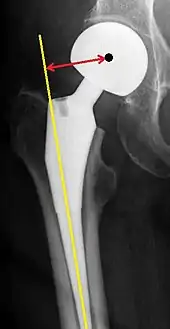

Post-operative projectional radiography is routinely performed to ensure proper configuration of hip prostheses.

The direction of the acetabular cup influences the range of motion of the leg, and also affects the risk of dislocation.[9] For this purpose, the acetabular inclination and the acetabular anteversion are measurements of cup angulation in the coronal plane and the sagittal plane, respectively.

Center of rotation: The horizontal center of rotation is calculated as the distance between the acetabular teardrop and the center of the head (or caput) of the prosthesis and/or the native femoral head on the contralateral side.[80] The vertical center of rotation instead uses the transischial line for reference.[80] The parameter should be equal on both sides.[80]